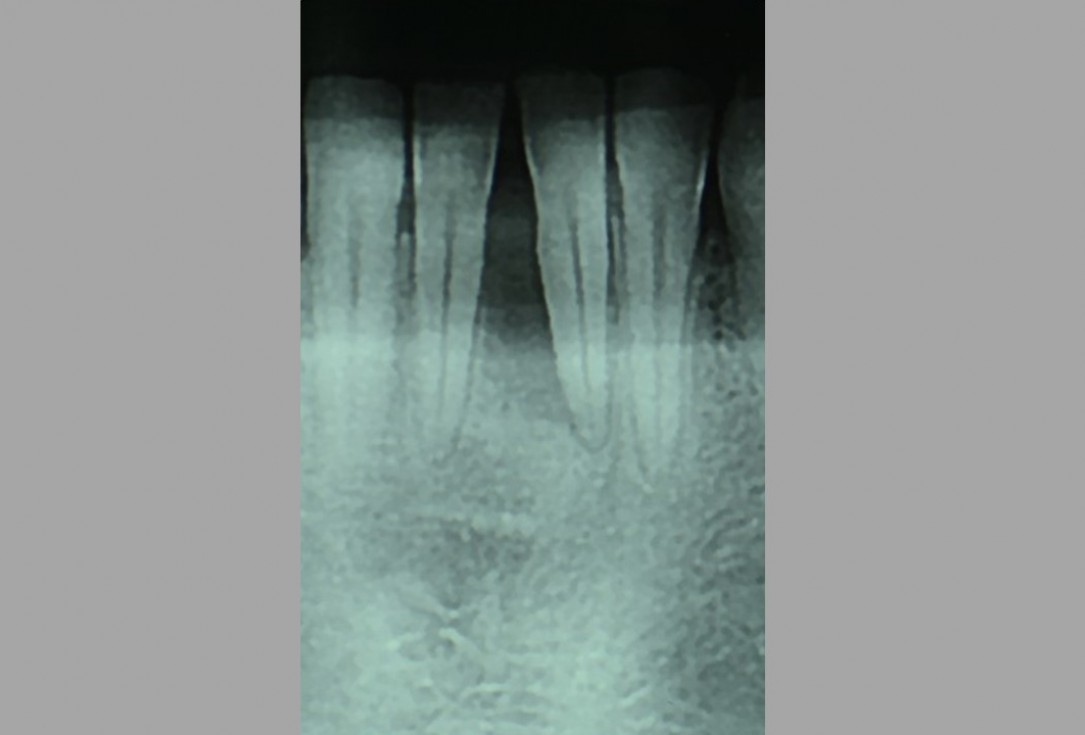

02/12 - Pre-operative radiograph. Deep intrabony defect at tooth 31.Two-wall intrabony defect treated using cerabone® and Straumann® Emdogain® - Dr. D. Rakasevic & Prof. Dr. S. Jankovic